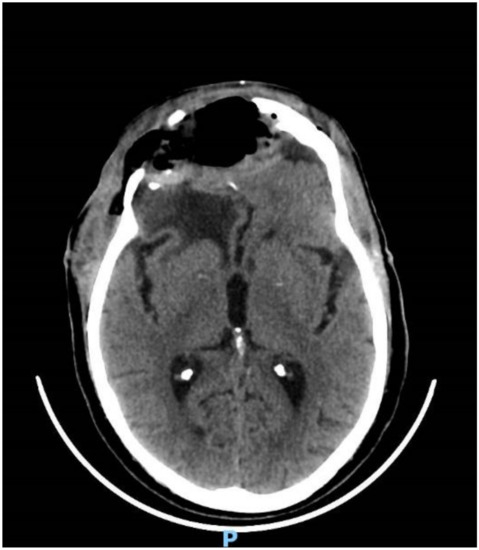

2. Case Report